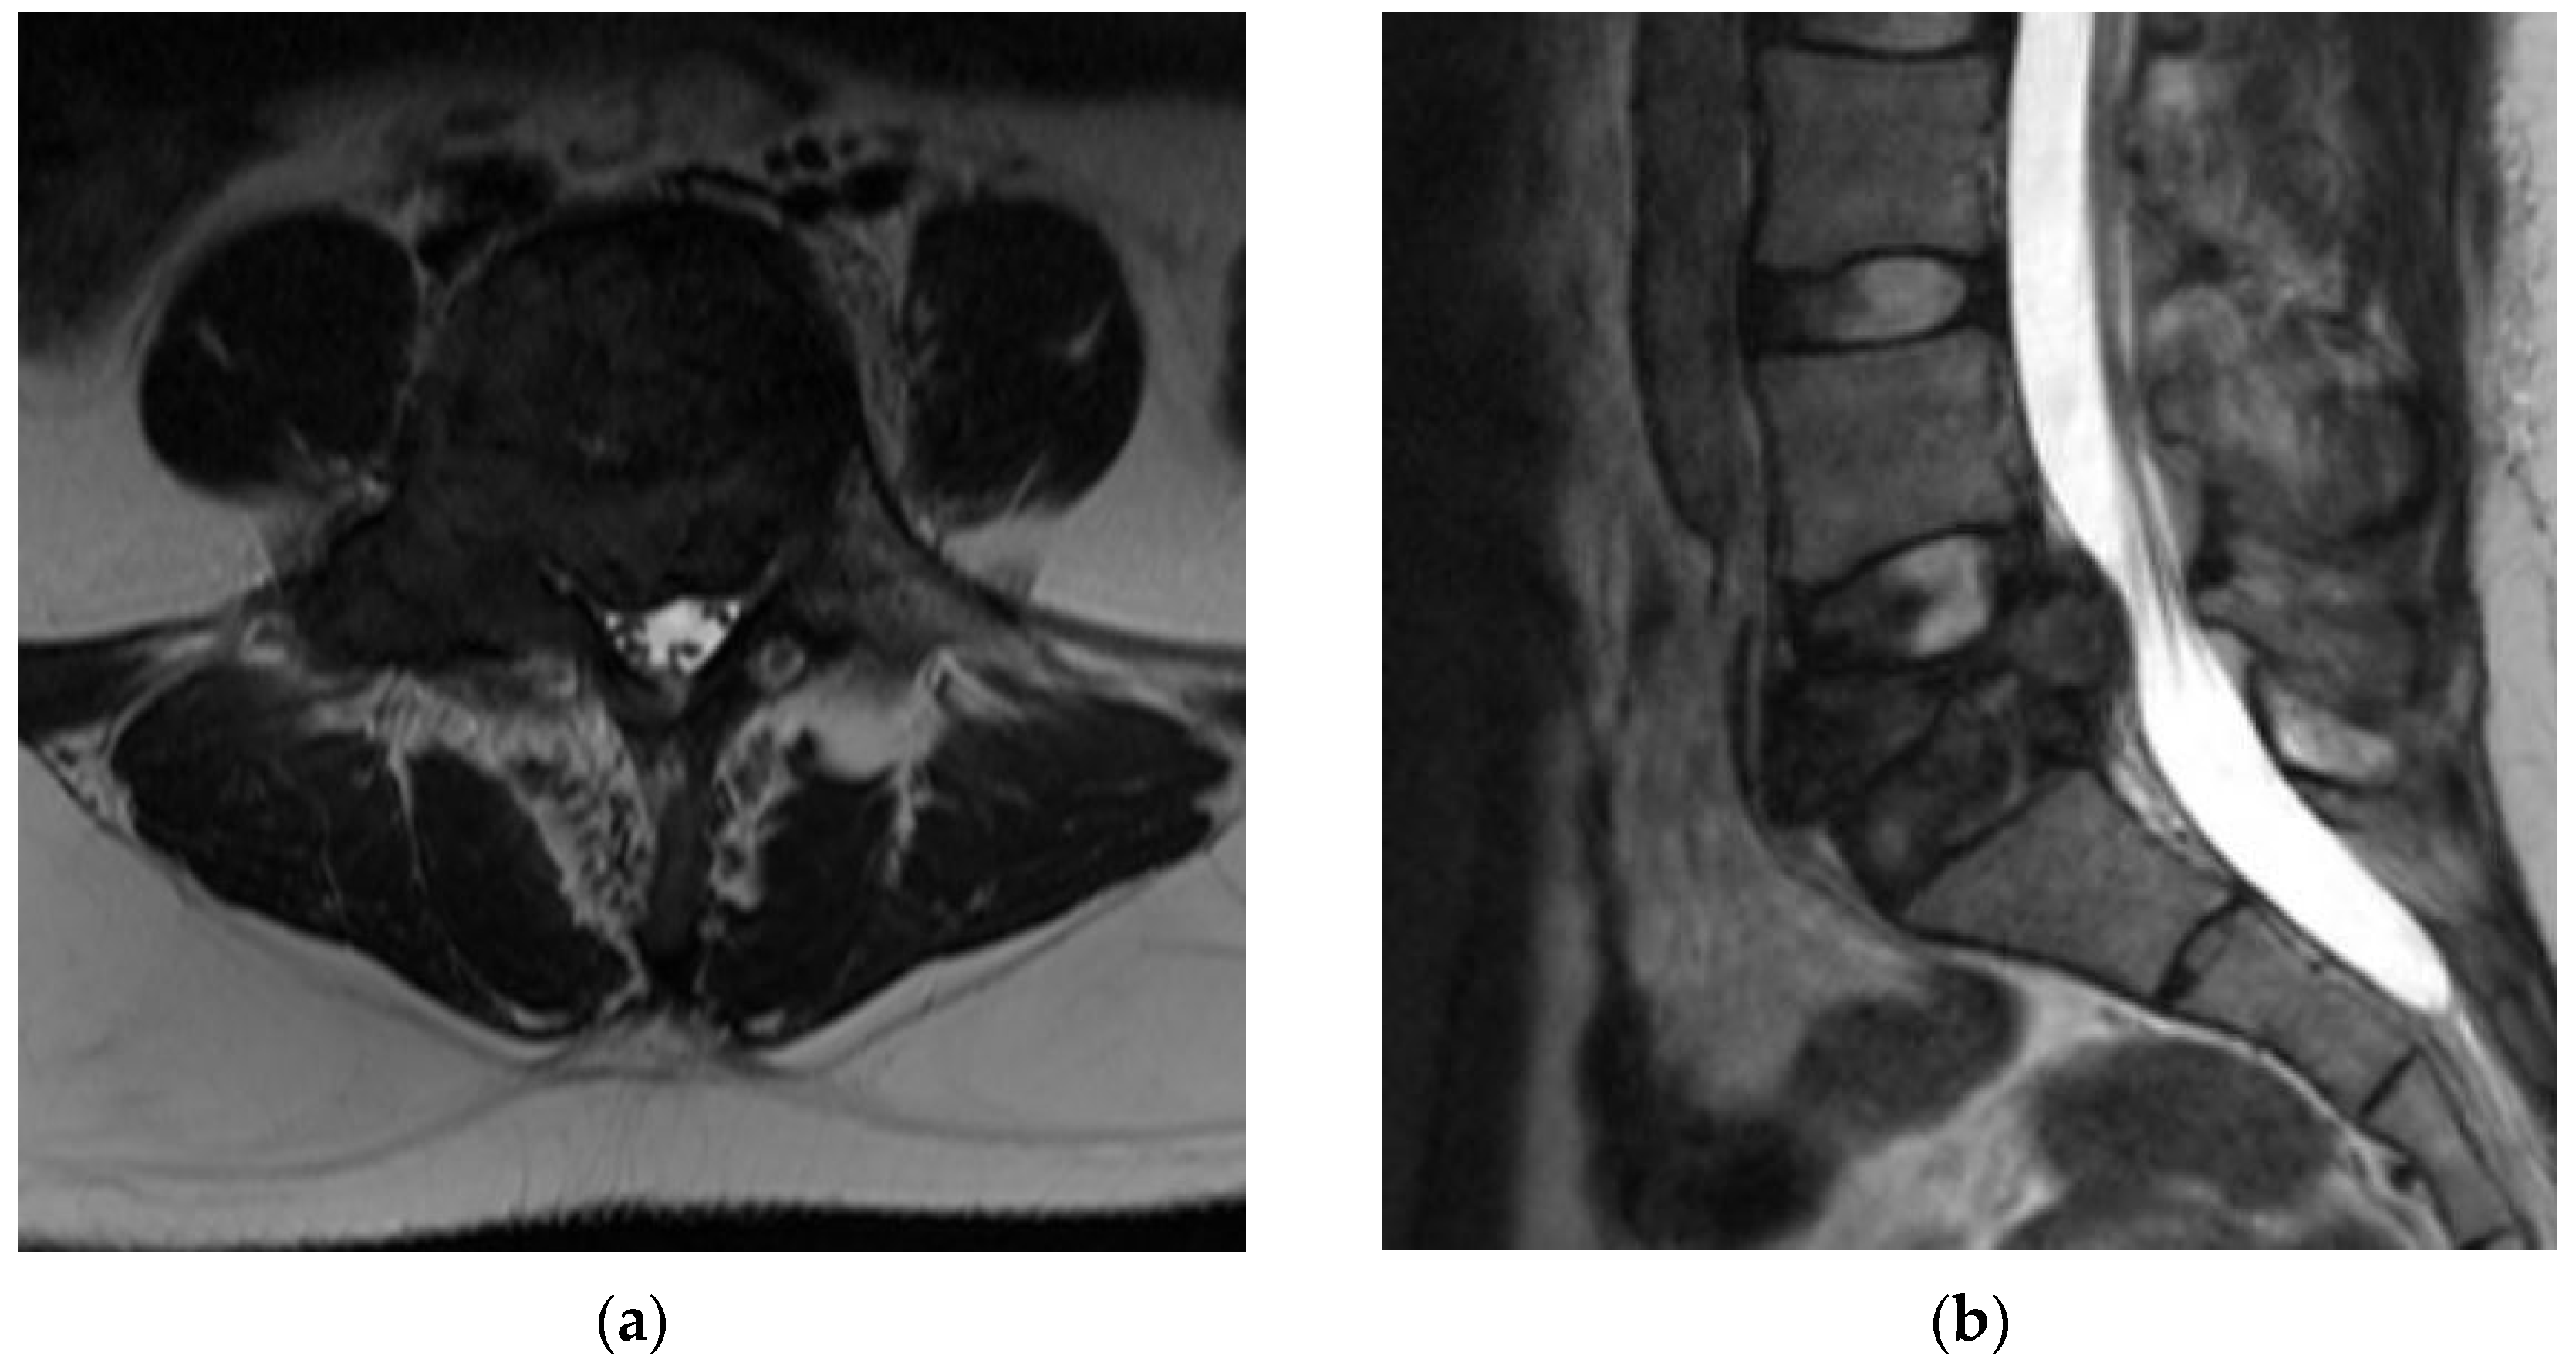

4.2.5. MRI